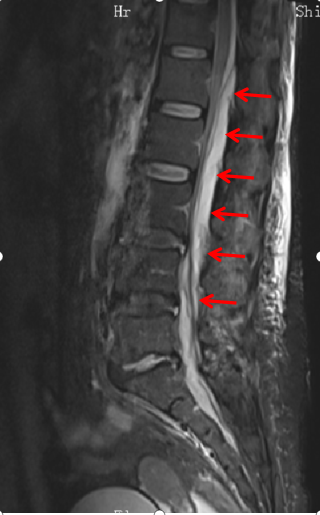

箭頭所指為鐘女士腰1至骶1節段膿腫

箭頭所指處可看出,受壓最嚴重部位脊髓已被擠壓成薄片狀